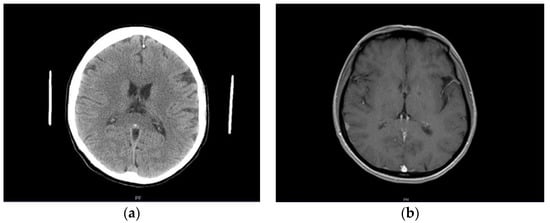

A previously healthy female patient, age 41, reported to the emergency unit (June 2019) due to recurrent episodes (2–3× per week) of severe headache and collapse. She mentioned first symptoms occurring a month before admission (May 2019). No abnormalities were observed in neurological examination or brain computed tomography (CT) at the time (Figure 1a). Outpatient MRI examination was performed 2 months afterwards (August 2019), which revealed no relevant findings apart from a small (size < 1 cm) focal lesion, consistent with a meningioma of the right parietal region (Figure 1b). Next, the patient underwent electroencephalography (EEG) in October 2019, which indicated secondary generalized seizures originating bilaterally in the temporal lobes. Based on the clinical image, the patient was diagnosed with structural epilepsy and received outpatient treatment (400 mg carbamazepine twice daily). As the treatment was poorly tolerated by the patient, who felt weak, generally unwell, and reported worsening headaches as well as repeated episodes of collapse, a decision was made to substitute carbamazepine with lamotrigine (100 mg twice daily). No symptom alleviation was observed. In fact, the patient reported intensification of headache and general weakness. The drug was discontinued (beginning of June 2020). Due to repeated episodes of collapse, a cardiological consultation was made which excluded cardiogenic causes of the clinical image. The patient observed further exacerbation of clinical symptoms: headaches appeared on a daily basis; the patient collapsed with an average frequency of four times per month (with brief loss of consciousness at times); no convulsions or involuntary urination were present. Apart from hypoesthesia on the left side of the body, confirmed by neurological examination, no other abnormalities were found at the time.

Figure 1.

(a) Normal brain image—CT examination in native phase; (b) contrast-enhanced T1-weighted axial MR cross-section indicating a small right parietal meningioma (arrow).